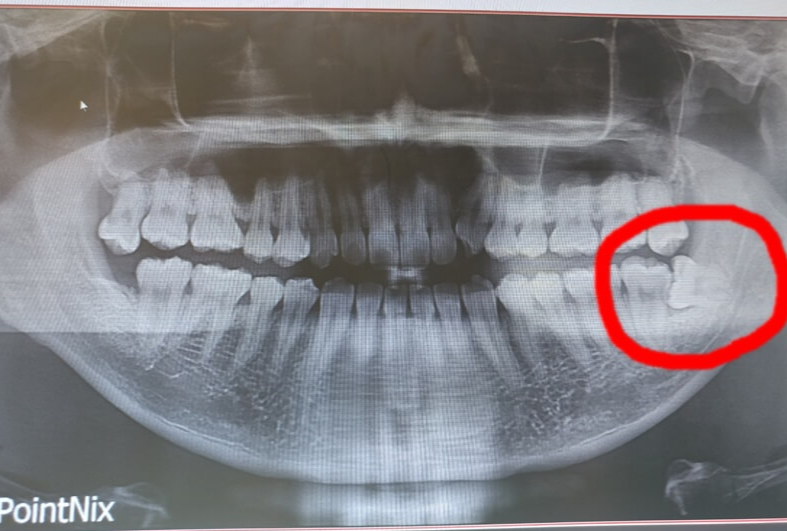

종류는 원심경사 매복 사랑니, 수평매복 사랑니, 수직매복 사랑니, 단순 매복 사랑니로 4개가 있는데 기울기에 따라서 다른 것으로 보면 됩니다. 위에 제 사랑니는 수평매복에 가깝다고 합니다ㅠ

저는 사진에서 보시면 아시듯 저는 사랑니 하나를 이미 7년전에 발치를 했었습니다. 의사가 별거 아니라고 잘뽑는다고 유혹해서 그때 당시 아무것도 모르고 발치를 했었죠. 전 그날 진짜 지옥을 맛봤습니다. 제 이는 엄청 튼튼한 이라고 합니다. 잘 부셔지지도 않는다고 합니다. 전 그날 1시간 30분동안 마취 하고 이를 뽑았고 이나 잇몸보다 턱이 더 아팠습니다. 진짜 턱이 빠지는 줄 알았어요. 의사가 한분만 뽑으신게 아니라 뽑다가 결국 한분이 교체 되어서 뽑았었습니다. 그 후 피가 너무 많이 나고 제대로 아물지도 않아서 거진 2주간 몸무게가 6kg이 빠질 만큼 고생했던 기억이 있었습니다. 그 후로 7년동안 너무 끔찍했기 때문에 뽑지 안았지만 계속 반대편 이가 불편한 것을 느끼던 참이였습니다. 그리고 다시 결심을 하고 다시 뽑으러 갔었고, 전 똑같은 경험을 또 한번 더 했습니다. 인간은 어리석고 같은 실수를 반복한다.